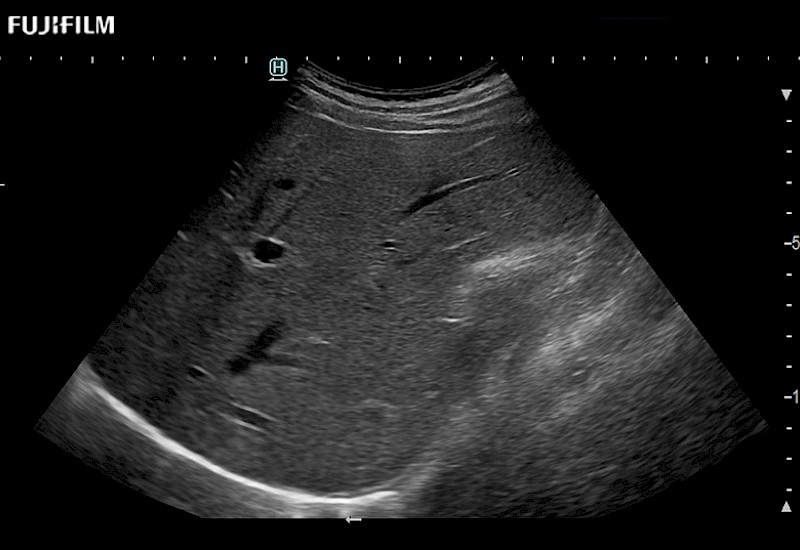

Our dedication to Laparoscopic Surgery allows us to offer superior image quality, outstanding system reliability and intuitive use of cutting edge technology.

The ARIETTA 750 incorporates all of the proven technologies and functions that medical professionals have come to expect from Fujifilm Healthcare.

ARIETTA 750 is the definitive diagnostic ultrasound solution for any clinical setting - Private Office, Imaging Center, or Hospital. The ARIETTA platform provides the ultimate in clinical performance with its state-of-the-art features and large user-friendly display.